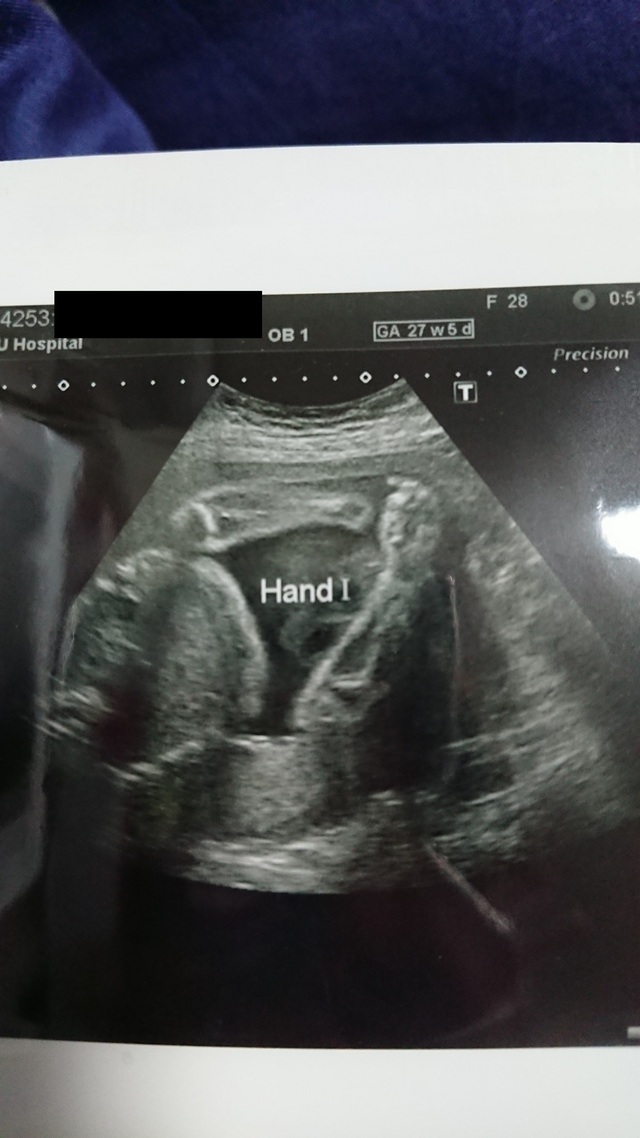

27週5日(27w5d・女の子)|bon420 さん(27歳)

エコー写真撮影時のエピソード:

初めてしっかり正面からお顔が見られた日。 こっちを向いて、お口をもぐもぐさせていました。手も近くにあったので、もしかしたら指しゃぶりをしようとしていたのかな~。

毎回頭の大きさ、お腹の大きさ、大腿骨の長さを測定してもらいますが、ちょっぴり頭が大きめだね、とのこと。元気に生まれてくれれば何でもいいよ♡ すくすく大きくなあれ♡